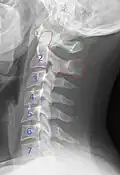

By convention, the cervical vertebrae are numbered, with the first one (C1) closest to the skull and higher numbered vertebrae (C2–C7) proceeding away from the skull and down the spine. The general characteristics of the third through sixth cervical vertebrae are described here. The first, second, and seventh vertebrae are extraordinary, and are detailed later.

X-ray of cervical vertebrae -